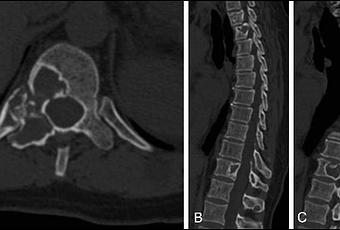

Esta técnica quirúrgica

inicia con una exposición de toda la columna dorsal, sacra y parte de la pelvis

mediante la disección y elevación de los músculos y tendones que tiene adheridos.

La disección se basa en reconstrucciones

en 3D y biomodelos. Luego hay que liberar la médula espinal de la

deformidad, lo que se denomina desanclaje medular. Una vez conseguido, se

identifican las vértebras a extirpar, habitualmente un bloque malformativo

bastante complejo. Para ello, dr usan técnicas microquirúrgicas, resección ósea

mediante motores de alta velocidad y bisturís piezoeléctricos para ir

extirpando el hueso sin tracciones sobre las estructuras más delicadas.

Finalmente, el resto de vertebras se extrae y se utiliza como injerto de hueso.

En estos pacientes, muchos de ellos con parálisis de los miembros, los huesos

pélvicos son débiles por lo que se complementa la estabilización mediante

tornillos y barras colocados alrededor del hueso para darle más solidez. Esta

técnica se emplea en aquellos pacientes

con deformidades graves, con curvas de más de 90 grados y desequilibrio pélvico

extremo. Todo esto supone un grave compromiso de los órganos internos, sobre

todo el pulmonar, produciendo una restricción respiratoria importante y

reduciendo enormemente su esperanza de vida. Esta Técnica se realiza enla Unidad de Neurocirugía de los Hospitales

Universitarios Virgen Macarena y Virgen del Rocío, de Sevilla en España.